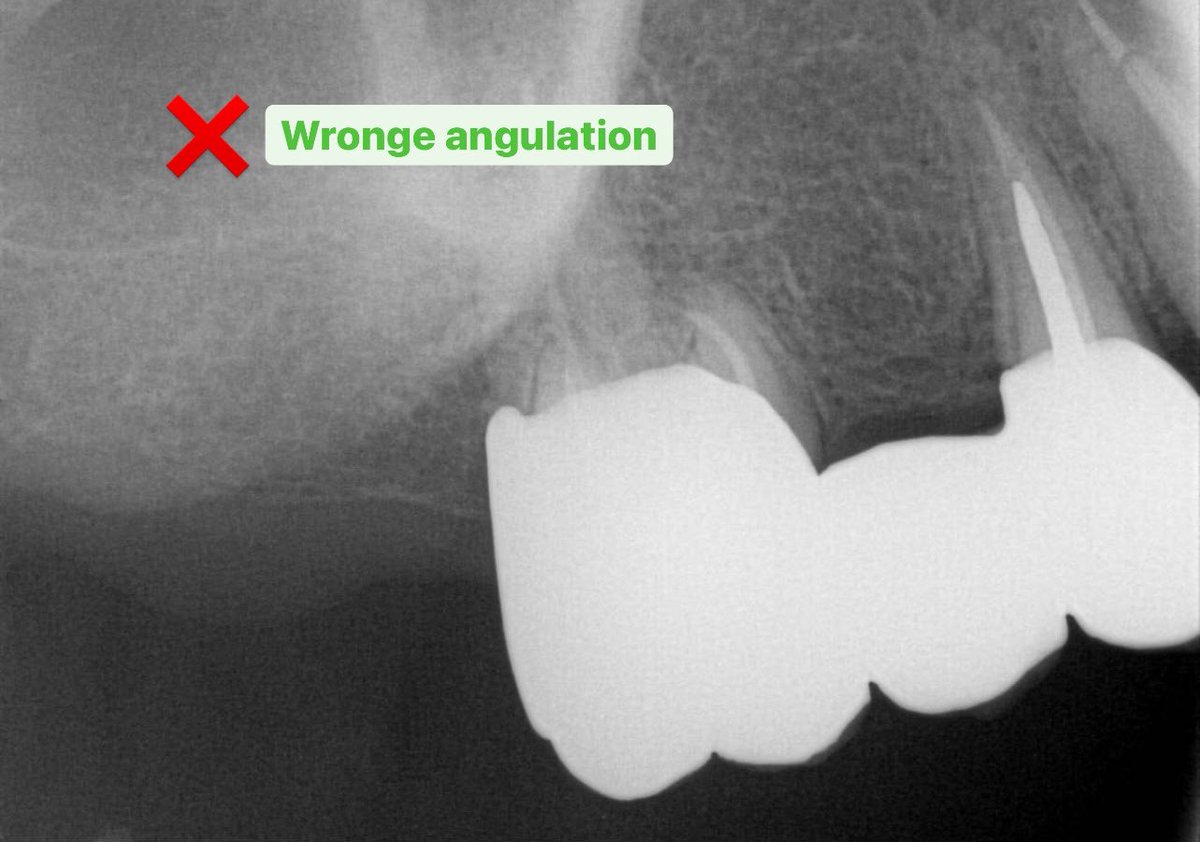

🟢لا تعتمد على أشعة زاويتها غلط لتقييم ال crowns fit or abutment fit ثمن تواصل، و في أشعة جديدة صحيحة تشوف المشكلة! ابدأ بالزاوية العمودية الصح من البداية و ارتاح >> bitewing + parallel PA